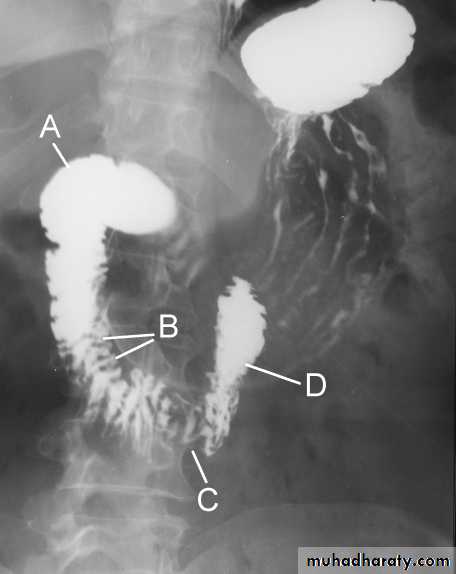

The Normal Anatomy of Stomach1- Shape.2-Size.3-Site.4-Anatomical parts.5-Mucosal pattern.

Normal Anatomy of DuodenumDuodenal cap.Duodenal loop

Barium meal Fluoroscopy + spot films Preparation